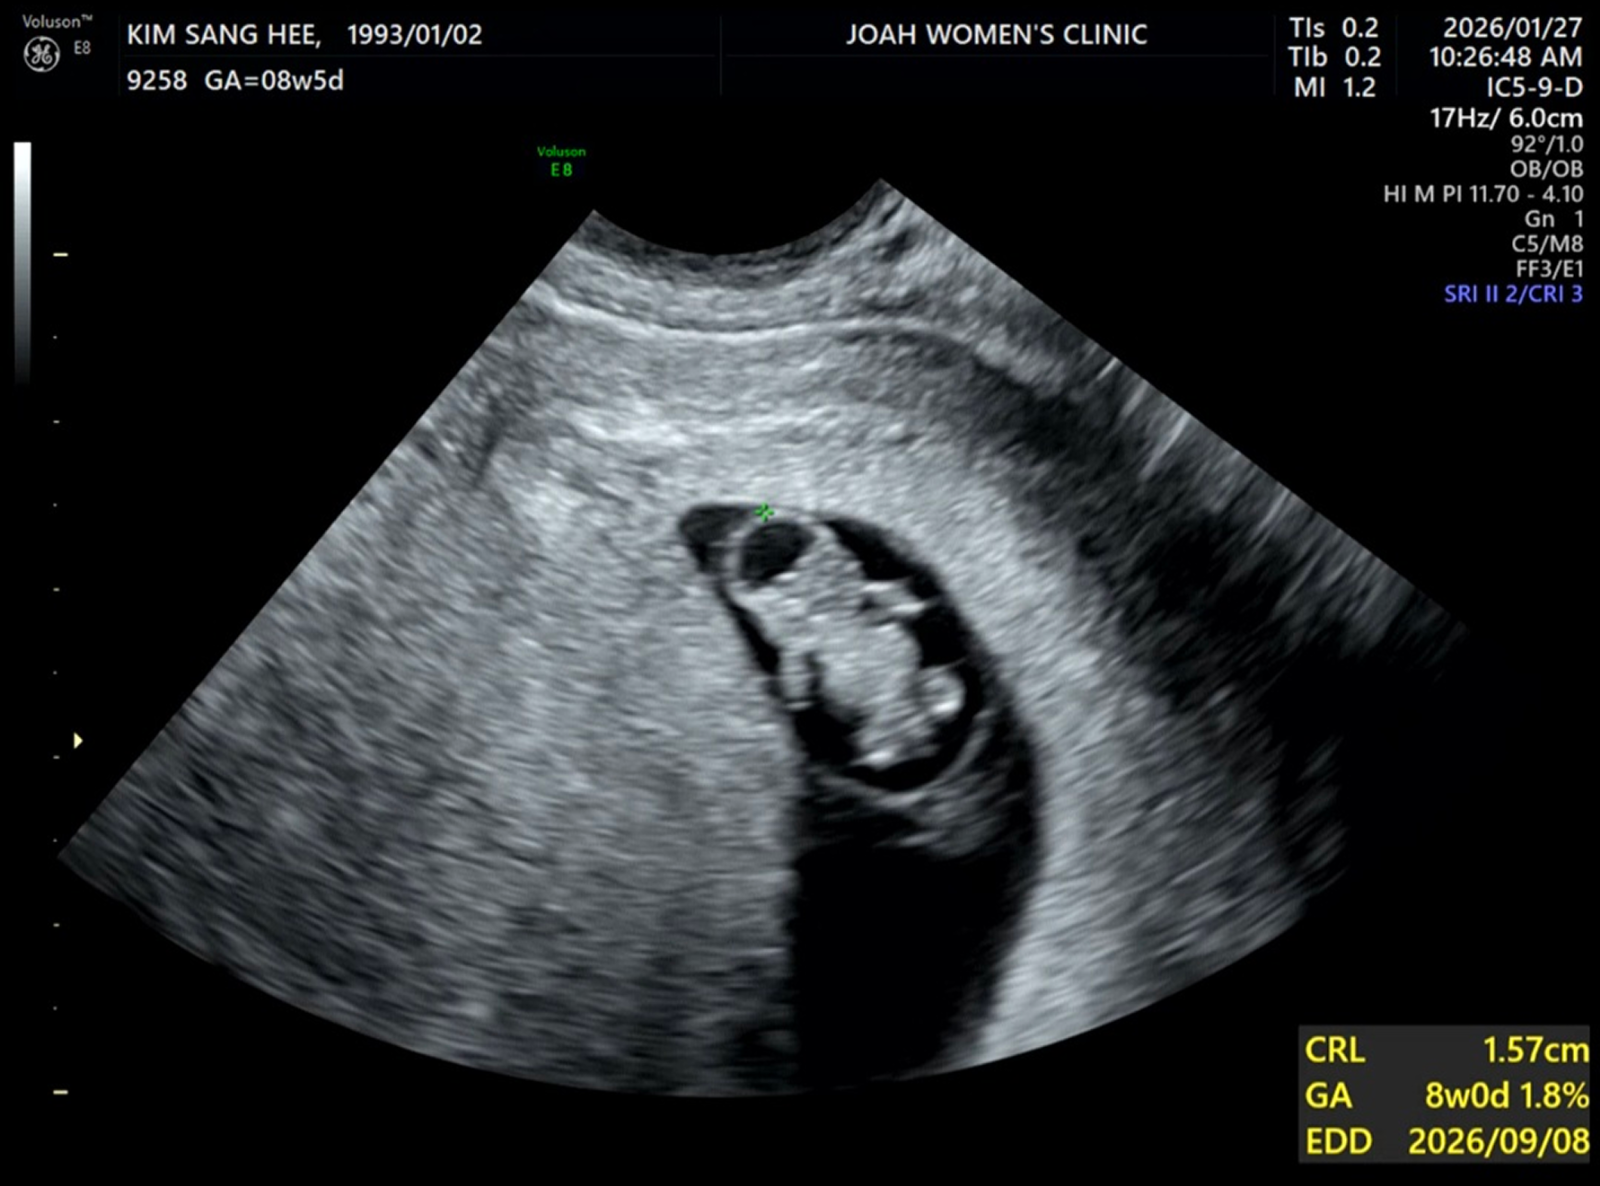

임신 주수를 계산하는 방법도 몰랐던지라 여러모로 산부인과를 늦게 가게 되었는데, 산부인과를 방문한 첫날, 나는 7주차 임산부라는 사실을 알게 되었다. 아이의 집이라는 난황과 7mm의 작디 작은 아이의 존재를 확인했고, 신체 변화가 많이 없어 임산부라는 자각조차 없었던 내게 초음파를 통해 들은 아이의 심장 소리는 수많은 감정을 들게 했다. 바쁘게 사느라 병원도 늦게 왔는데, 일한다고 바쁘게만 지냈는데, 그래도 너는 내 안에서 이렇게 크고 있었구나. 임신 확인서와 필요한 검사에 대한 안내들을 받고 집에 돌아오는 길, 처음으로 ‘엄마’라는 아이덴티티가 자리잡기 시작했다.